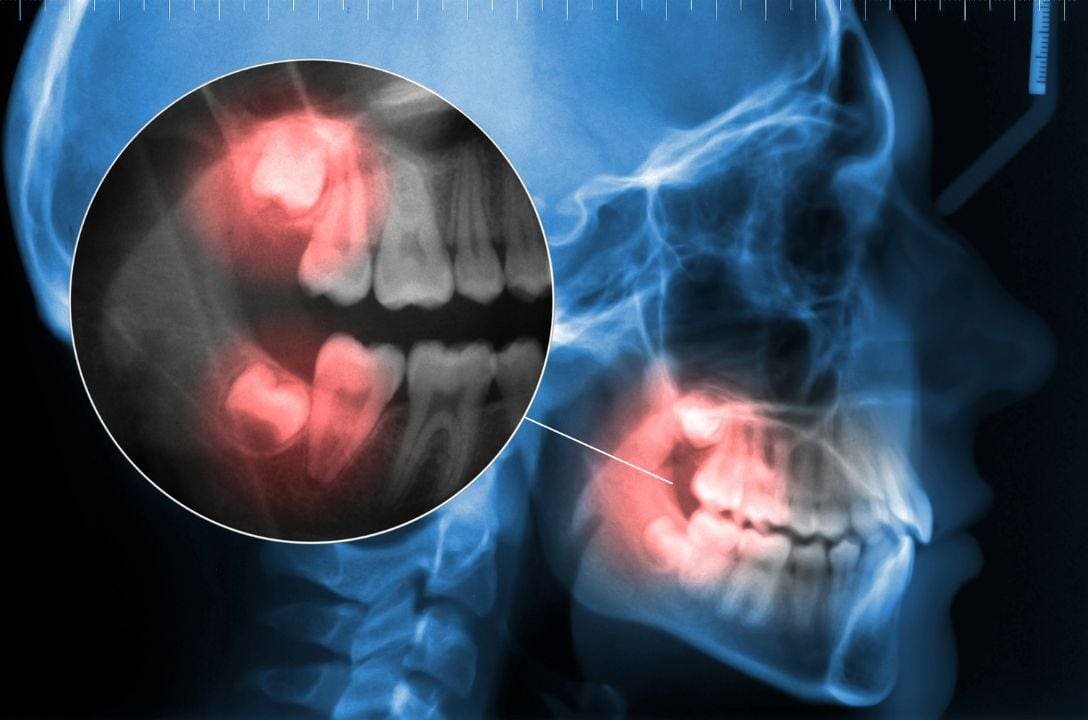

O dente siso é o último a nascer, geralmente entre os 17 e 25 anos, e muitas vezes não encontra espaço suficiente na boca. Por isso, pode nascer torto, pressionar outros dentes ou até ficar preso na gengiva, causando dor, inflamação e infecção. Em alguns casos, o dente siso nem chega a nascer por completo, mas mesmo assim pode provocar complicações.

Antes da extração, o dentista solicita exames como radiografias ou tomografias para avaliar a posição do dente e planejar a cirurgia. Em seguida, o paciente recebe anestesia local e o dente é retirado de forma segura.